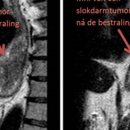

MRI van de slokdarm

Een groot deel van patiënten met slokdarmkanker wordt behandeld met chemoradiotherapie (combinatie van bestraling en…